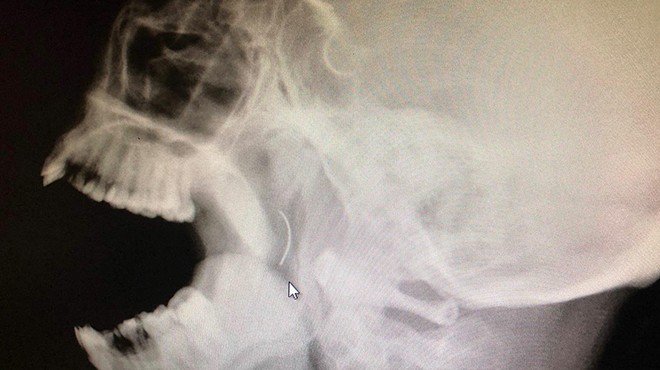

İZMİR - Soma'da yaşayan Meltem Cansız, 1999 yılında bademcik şikayeti nedeniyle ailesi tarafından Soma Devlet Hastanesi'ne götürüldü. Burada yapılan kontrolün ardından Cansız'ın ameliyat edilmesine karar verildi. Ameliyat sırasında ise dikiş atıldığı sırada iğne kırıldı. Kırılan iğne parçası Cansız'ın boğazında unutulurken, 14 yaşındayken boğazındaki ağrıların artması üzerine gittiği üniversite hastanesinde MR çektirmek için makineye girdiğinde MR çekilemedi. Tekrar tekrar denenmesine rağmen MR çekilemeyince doktorlar o bölgede metal bir parçanın olabileceği ihtimali üzerinde durarak Cansız'ı röntgen filmine yönlendirdi. Çekilen röntgen filminde 3 yaşındayken olduğu ameliyatta unutulduğu anlaşılan iğne parçasına rastlandı. Doktorlar iğnenin şah damarına yakın olduğunu söyledi.

Şuan 21 yaşında olan ve lise öğreniminden sonra sağlık sorunları nedeniyle üniversiteye hazırlanamayan Meltem Cansız, İzmir'de özel bir hastanede geçirdiği başarılı ameliyatla 18 yıldır birlikte yaşadığı iğneden kurtuldu. Ameliyatı gerçekleştiren Kulak Burun Boğaz Uzmanı Doç. Dr. Çağlar Çallı, iğnenin şah damarına çok yakın olması nedeniyle riskli bir operasyon gerçekleştirdiklerini belirterek, şunları söyledi:

"Hastamız Meltem Cansız'ın boğazından ameliyatta unutulan iğneyi başarılı bir operasyonla çıkardık. Yaklaşık 18 yıldır hastamızın boğazında duruyordu. Çıkartma esnasında kırılabilirdi. Çok riskli bir ameliyattı. Üç yaşında bademcik ameliyatı olmuş ve iğne unutulmuş. 17 yaşına geldiğinde bir MR filmi istendiğinde bu iğnenin unutulduğu ortaya çıkmış. İğneden dolayı MR çekilememiş. baş ve boyun bölgesinde bir uyarı alınmış ve bu bölgede metal bir cismin olduğu söylenmiş. Daha sonra çekilen röntgen filmlerinde iğnenin unutulduğu görülmüş. Hastamız bir üniversite hastanesine gitmiş. Orada iğnenin çıkartılması için bir ameliyat olmuş. Fakat çıkarılamamış. Yeniden yapılan kontrollerde ise iğnenin çıkartılamayacağı ve çok riskli olduğu söylenmiş. Bu iğnenin bir zararı olmayacağı ve onunla birlikte yaşamaya alışması söylenmiş. Hastamızın rahatsızlığı devam etmiş. Başarılı bir operasyonla iğneyi çıkarttık."

"Tabii ki riskli bir durum. Bademcik ameliyatı sırasında kırılan iğnenin orada kalmış. Daha öncede söylendiği üzere iğnenin olduğu bölgenin şah damarına yakın olmasından dolayı riskli bir ameliyattı. Bunlara zarar vermeden çıkartmak lazım. Riskin farkında olarak ameliyata başladık. Bizi zorlayan ve terleten bir ameliyat oldu. Ameliyat sırasında iğneyi alırken, parçalamadan iğneyi almak ve diğer damarlara organlara zarar vermemek için çalıştık. Sonuçta 18 yıldır orada duran bir metal parçasına dokunduğumuzda tuz buz olabilirdi. Vücudun sağlam dokularına zarar vermeden iğneyi bulduk. Başarılı bir ameliyat oldu ve iğneyi tek parça çıkardık. Hastamız da biz de mutluyuz." (DHA)